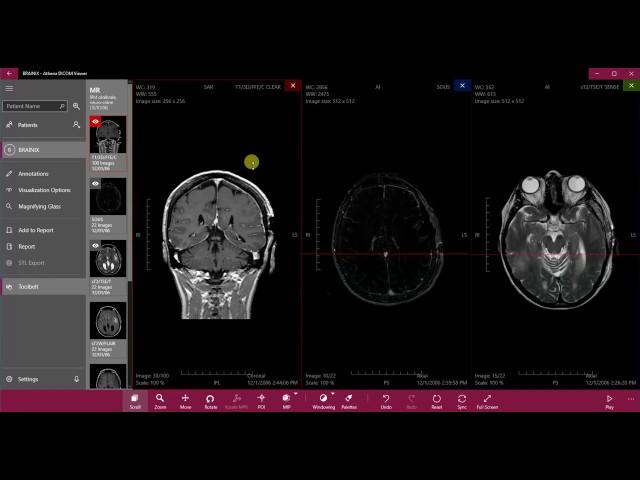

Opening Studies - Athena DICOM Viewer

Athena DICOM